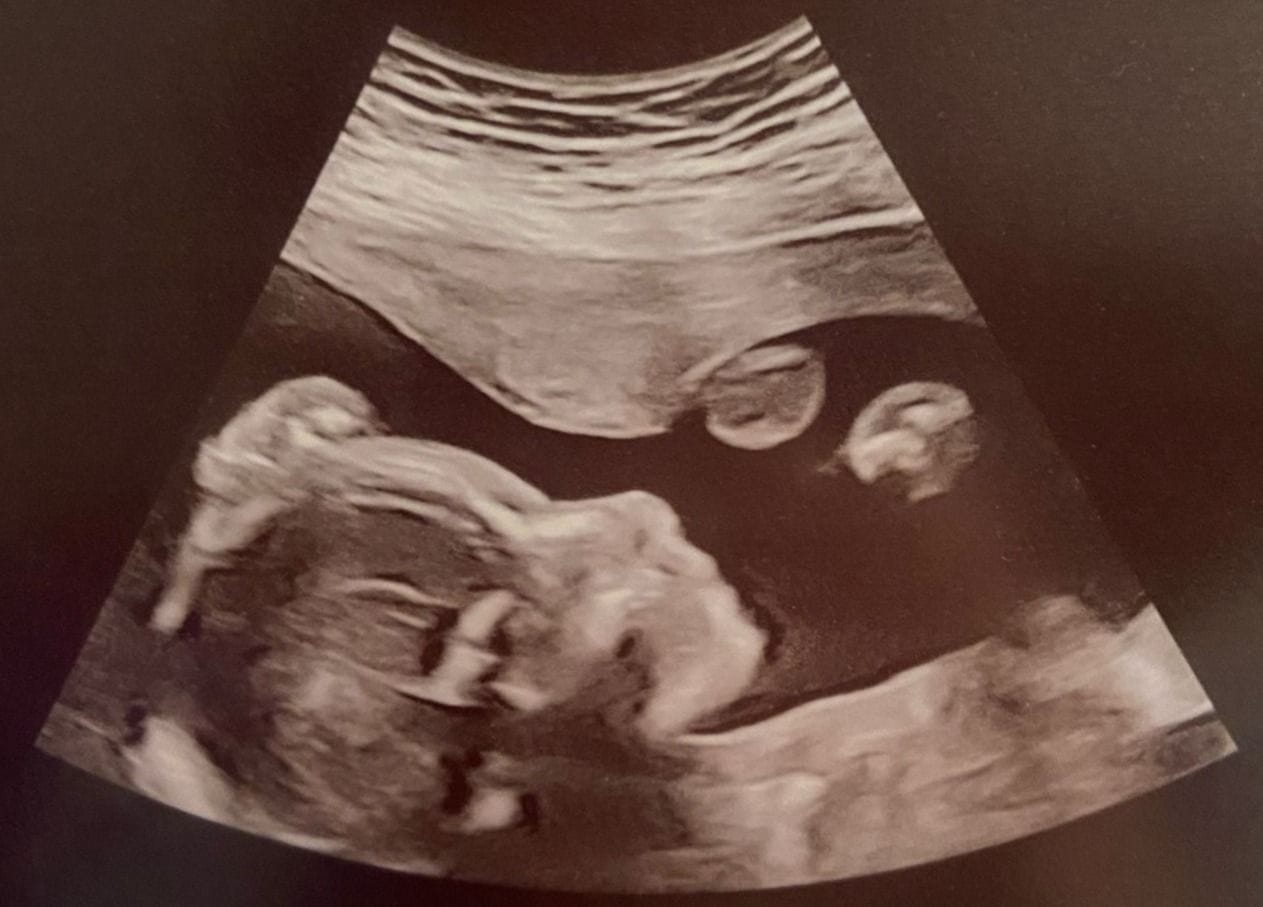

20250315_122339

Source: Skyler Espinoza